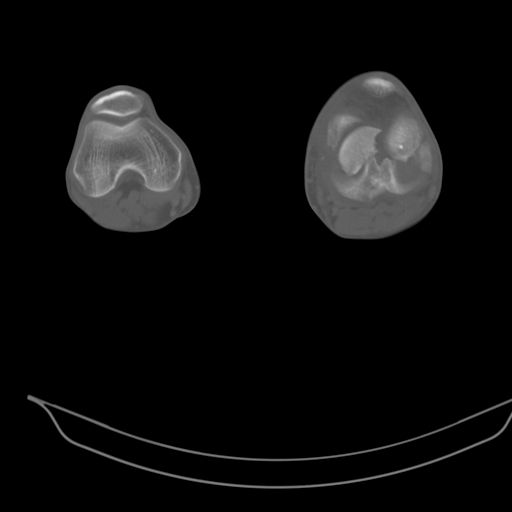

CT shows major bony fragments which are markedly rotated .With this amount of bony damage,you probably should attempt to get reasonably loooking knee with ORIF and thn if he needs a TKR due to pain a few years from now, then tleast you have something looking like a knee that you can replace rather than having to use revision knee for a primary TKR now. 4 weeks is not too long .what is the condition of soft tissues?

При внутрисуcтавных переломах трехмерные (3D) изображения, кроме красивого снимка, не дают полную информацию о состоянии отломков, самыми информативными являются корональные срезы на КТ и обычная длинная ренгенограмма конечности для сравнения оси конечности.

Фронтальные внутрисуставные переломы мыщельков бедра, так называемые Hoffa fracture, не частые, но встречающиеся переломы, в основном они связаны с травмой высокой энергией.

В зависимости от смещения рекомендуется сопоставление костных фрагментов с последующей жесткой фиксацией.

В вашем случае доступ будет медиальный, сопоставить развернутый медиальный мыщелок и фиксацию надо произвести в передне-заднем

направлении шурупами 4.5 мм в диаметре, углубив головку шурупов под хрящ, а поперечную фиксацию - межмыщелковыми шурупами. Желательно применить шурупы 6.3 мм в диаметре. Дополнительная Buttress technique пластина предотвратит перелом от скольжения.

Даже при сросшемся переломе мыщелка рекомендуется реконструктивная операция для предотвращения последующих варус или вальгус деформации.

Место образовавшего костного дефекта после разворота мышелка заполняется спонгиозной аутокостью. Костная пластика применяется даже

в свежем случае.

Под наркозом редрессация, ранняя разработка сустава после операции, нагрузка на конечность через 12 недель помогут удержать без коллапса

фиксацию и поможет больному восстановить функции конечности без артропластики коленного сутава.